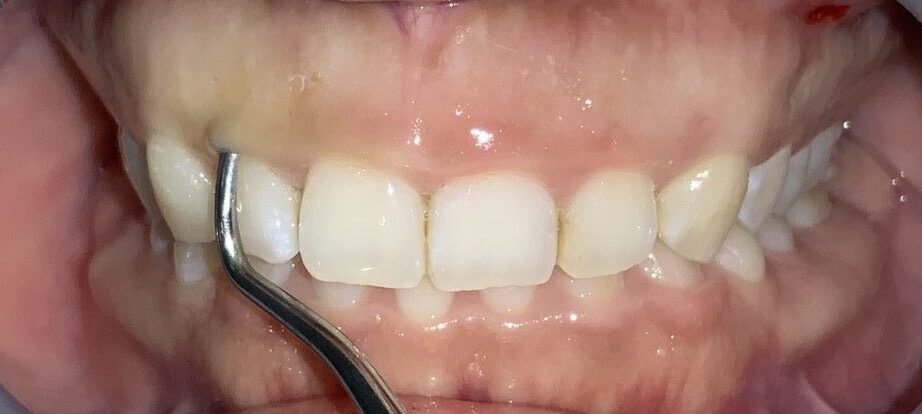

犬歯です。

歯ぐきの部分が大きいですね。しかも歯ぐきが薄いので、検査器具が歯ぐきの下から透けています。

最後に4番目の歯です。

1本1本、歯ぐきの被り方や厚みは違いますから、その点を見極める診察が大切です。

まずは1本だけ治療をして、切除範囲や大きさ、見え方、厚さなど気になる部分を患者様に確認をして頂きます。

患者様のご希望により、大きめの切除と歯槽骨の整形を行なっています。歯も、歯ぐきも歯槽骨もとてもキレイです。